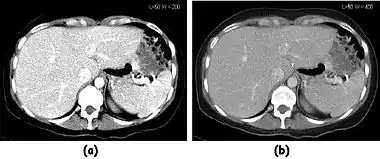

Fig. 7.15.2: Effect of window width and level on CT image display: (a) Level = 50; Width = 200. (b) Level = 50; Width = 400. The image in (a) is displayed with greater contrast and appears noisier than that in (b). |  Fig. 7.15.3: Effect of window width and level: (a) Level = -600; Width = 1700. (b) Level = -60; Width = 400. Image (a) displays the lung tissue more clearly, while image (b) can be used to highlight any pulmonary lesions. |

- Examples of image display manipulation are shown in the two figures above. In Figure 7.15.2, the same image of a slice through a patient's liver is displayed using a relatively narrow window (high contrast) and also with a wide window. The image with the narrower window appears noisier, but this is merely a reflection of the fact that the gray scale is spread over a narrow range of CT-numbers.